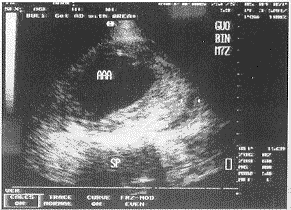

中国超声医学杂志991038 患者男,72岁。1998年2月,患者无意中发现脐部左上方有一包块。超声检查显示:髂总动脉分叉前腹主动脉呈梭形扩张,长度110mm,最大内径70mm。瘤壁呈不规则增厚,最大厚度(后壁)18mm,横切面显示后壁有半弧形无回声区(15mm×8mm)。超声诊断:腹主动脉瘤并夹层瘤。1999年2月10日,患者感到腰部持续性钝痛,向臀部放散。2月11日因疼痛加剧而入院。查体:体温37℃,血红蛋白:97g/L,脐部左上方可触及20cm×15cm搏动性包块。入院第二天,体温37.8℃,血红蛋白:89g/L,超声所见:腹主动脉瘤大小较一年前无明显变化,但瘤壁有明显增厚,尤其是后壁增厚至36mm,后壁内原有的夹层瘤已由无回声变成低回声,考虑有机化,可显示夹层瘤的破裂口(图1),横切面显示瘤体外周左侧有低回声区,提示腹膜后血肿形成(图2)。肝段腹主动脉,髂总动脉内径正常,双侧股动脉内显示大范围斑块。第三天,体温38.2℃,血红蛋白76g/L。入院第四天,又出现腰部剧痛,仍有发热,体温38℃,血红蛋白降至70g/L,超声所见:腹主动脉瘤后壁除原有的夹层瘤外,在其浅层可见新出现的液性无回声区(40mm×25mm×7mm),有破裂口与腹主动脉瘤相通,并显示有血流信号,超声诊断:腹主动脉瘤并夹层瘤再形成。第五天上午,再次复查超声:腹主动脉瘤体外周左侧低回声区有明显扩大,提示血肿增大(图3)。血红蛋白已减少至54g/L,体温38℃。当晚患者突感腰部绞痛,难以忍受,伴有全身大汗,20分钟后意识突然丧失,腹部膨隆,继而心跳、呼吸停止,经抢救无效,死亡。临床诊断:腹主动脉瘤并夹层瘤破裂。

AAA:腹主动脉瘤,↓:陈旧性夹层瘤破口,↓↓↓:增厚的动脉瘤后壁

图1 腹主动脉纵切面